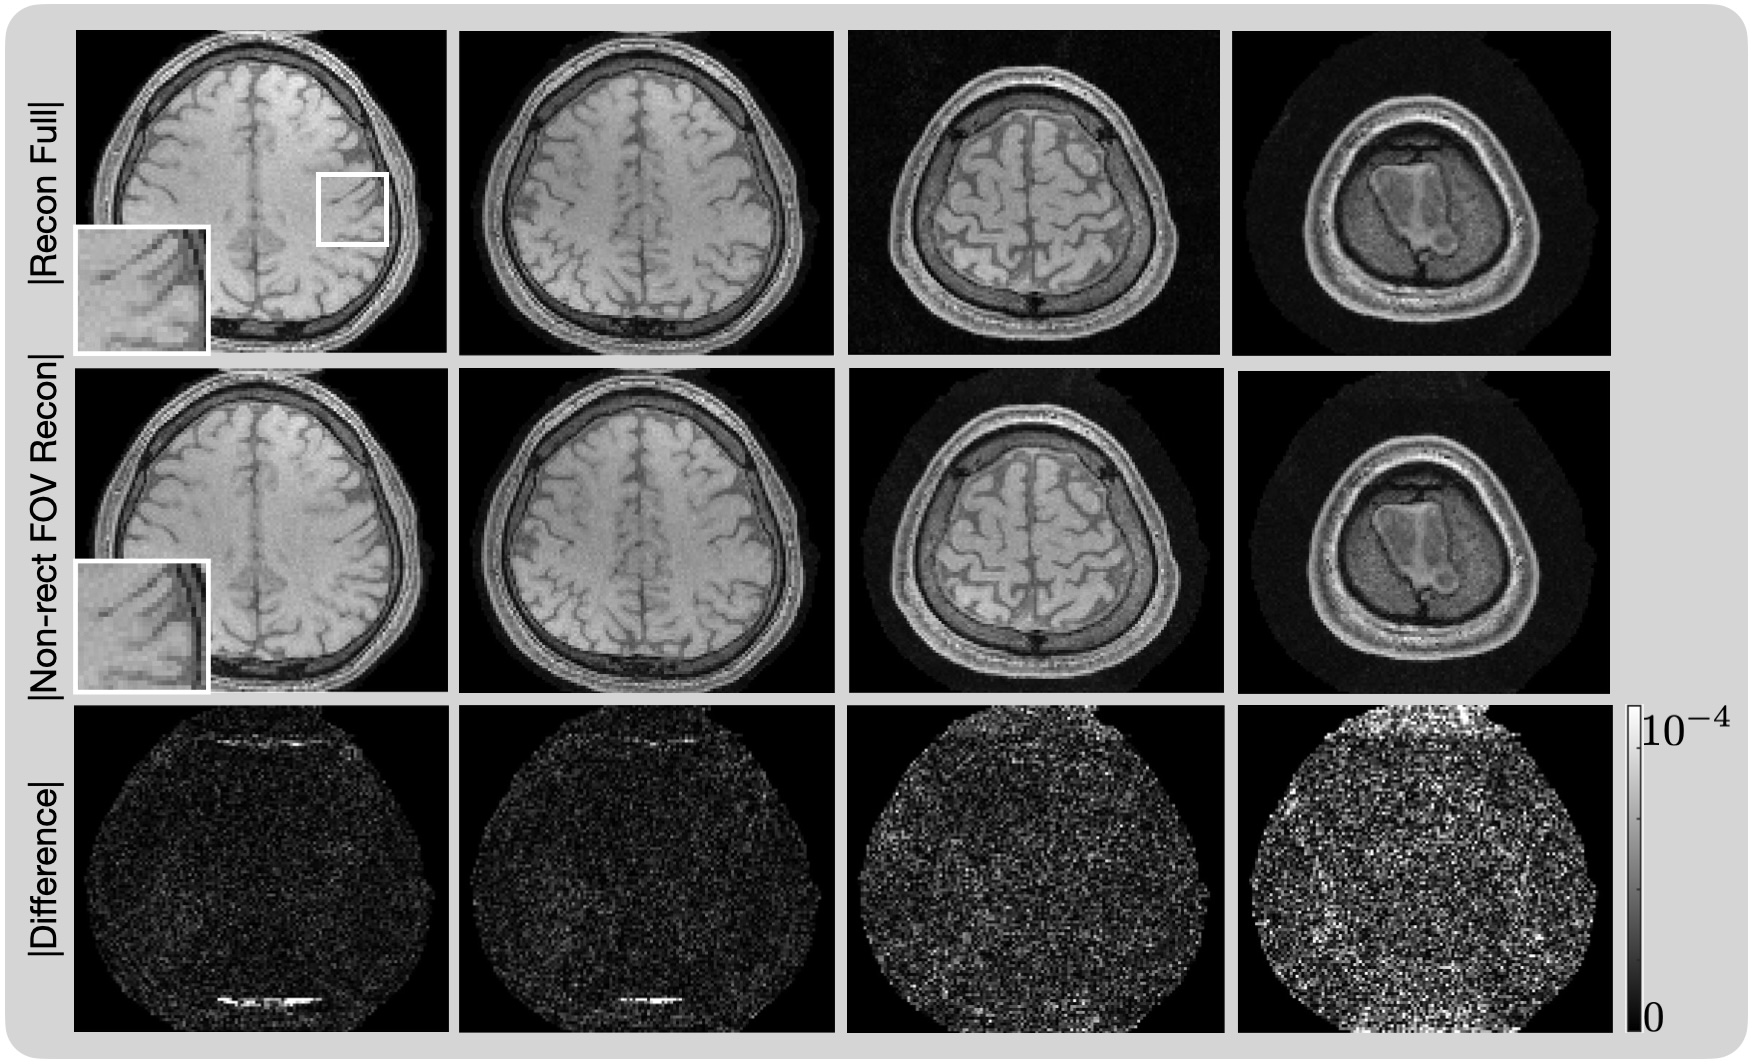

Figure 11 shows reconstructions using the non-rectangular FOV and compares them to the fully-sampled reconstructions for several slices of a human brain. The sampling pattern of the non-rectangular FOV had a 95%percent9595\%95 % sampling burden. The differences for all slices range from 00 to 104superscript10410^{-4}10 start_POSTSUPERSCRIPT - 4 end_POSTSUPERSCRIPT. As in all other examples, taking advantage of the non-rectangular FOV reconstructs a high-quality image with a reduced sampling burden. The significant errors in the reconstruction are due to subject motion in between the full sampling pattern and the reduced sampling pattern; this would largely be eliminated if data were collected during a single scanning protocol.

Figure 11: Magnitude image reconstructions using the direct method for four axial slices of a brain using data collected with an 8888 coil array. The sampling pattern of the non-rectangular FOV had a burden of 95%.